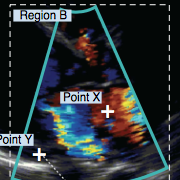

PI-RADS v2.0 Report Plugin

PI-RADS v2.0 Report Plugin

Easily represent and compute the PI-RADS v2.0 score, with a full graphic user interface. The score is assessed on prostate MRI. Images are obtained using a multi-parametric technique including T2 weighted images, a dynamic contrast study (DCE) and DWI. The goal of PI-RADS score is to improve diagnosis and treatment of prostate cancer. The plugin produces a complete report, including diagrams, in high quality DICOM PDF format.

Learn more in the PI-RADS v2.0 Report Plugin User Manual.